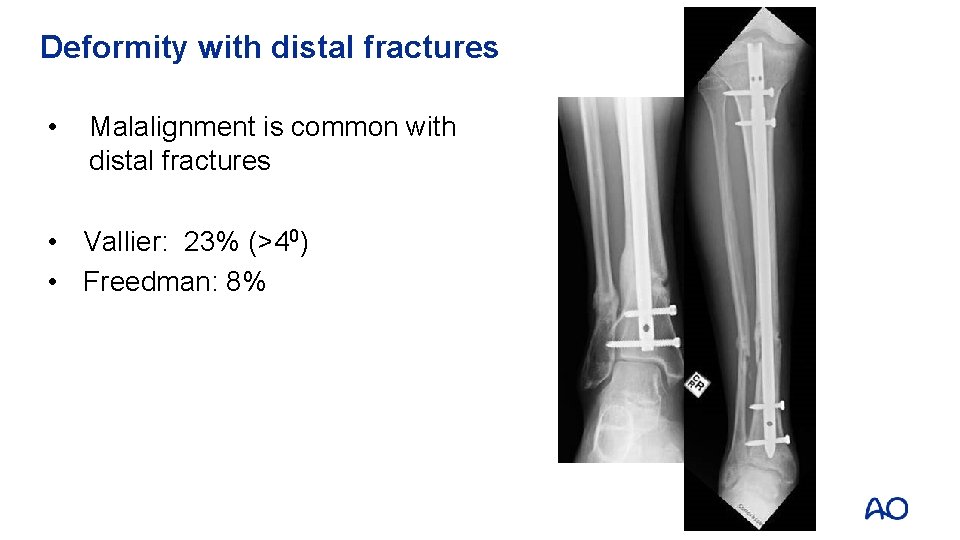

Deformity with distal fractures • Malalignment is common with distal fractures • Vallier: 23% (>40) • Freedman: 8%

Reduction aids for distal fractures • Pointed (percutaneous) clamps • External fixation • Steinman pin • Fibular fixation • Blocking screws

Benefits of plates for distal fractures • Less malalignment • High union rate Vallier et al (J Orthop Trauma. 2011; 25: 736– 741) Vallier et al, (J Orthop Trauma. 2012; 26: 327– 332)